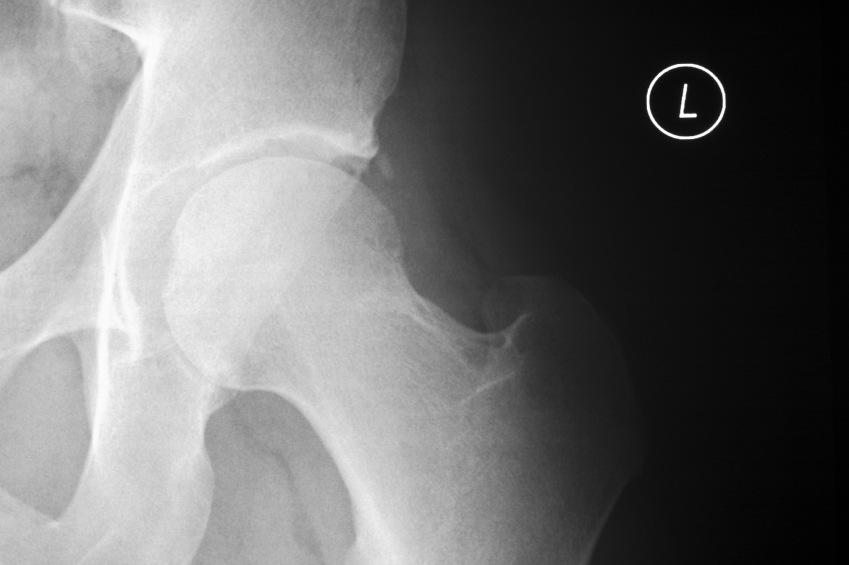

Bij patiënten met heupartrose die door de fysiotherapeut zijn behandeld met gedragsgeoriënteerde oefentherapie (GRADIT), is het risico op een gewrichtsvervangende operatie drie keer zo laag als bij patiënten die zijn behandeld volgens de richtlijn. Dit blijkt uit een publicatie van onderzoekers van het NIVEL in het wetenschappelijke

Op de lange termijn resulteren beide behandelingen in minder pijn en beperkingen in activiteiten, zowel bij mensen met heup- als knieartrose. Echter, bij mensen met heupartrose vermindert de GRADIT-behandeling op de korte en middellange termijn de pijn en beperkingen meer dan de behandeling volgens de richtlijn. Bovendien blijkt dat het risico op een gewrichtsvervangende operatie bij mensen met heup- artrose die de GRADIT-behandeling krijgen bijna drie keer zo laag is. NIVEL-onderzoeker Martijn Pisters: “Dit is een bijzonder resultaat. Het betekent dat een gericht oefenprogramma een gewrichtsvervangende operatie kan voorkomen, of in ieder geval kan uitstellen. Natuurlijk is hiernaar nog meer onderzoek nodig, want wij waren er niet primair op gericht verandering in het aantal operaties aan te tonen.”